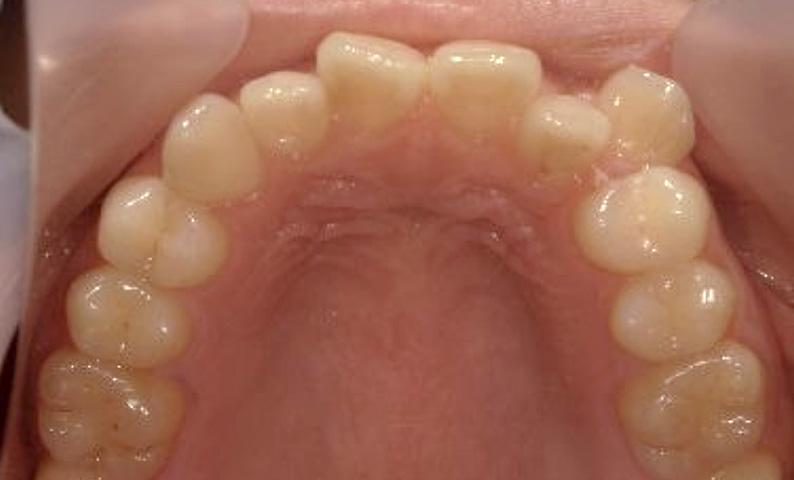

症例_023 上顎だけの部分矯正

治療期間:9ヶ月金額:30万円+税女性前歯のガタガタ上の前歯だけ

| Before | After |

|---|---|

|